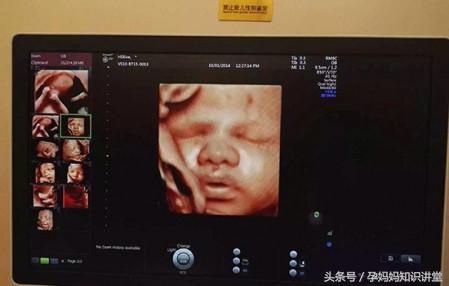

4、四维彩超的检查时间会有点长,大概有半个小时左右。因为医生会花大量的时间仔细看胎儿是否有肢体缺陷等。

5、四维彩超检查也被称为“大排畸”检查。换言之,就是可以大范围的判断胎儿是否有缺陷。当然,由于胎儿发育过程还没有完,并且现有的机器设备不能非常清晰的看清楚胎儿所有的肢体器官,所以,超声诊断符合率不能达100%。